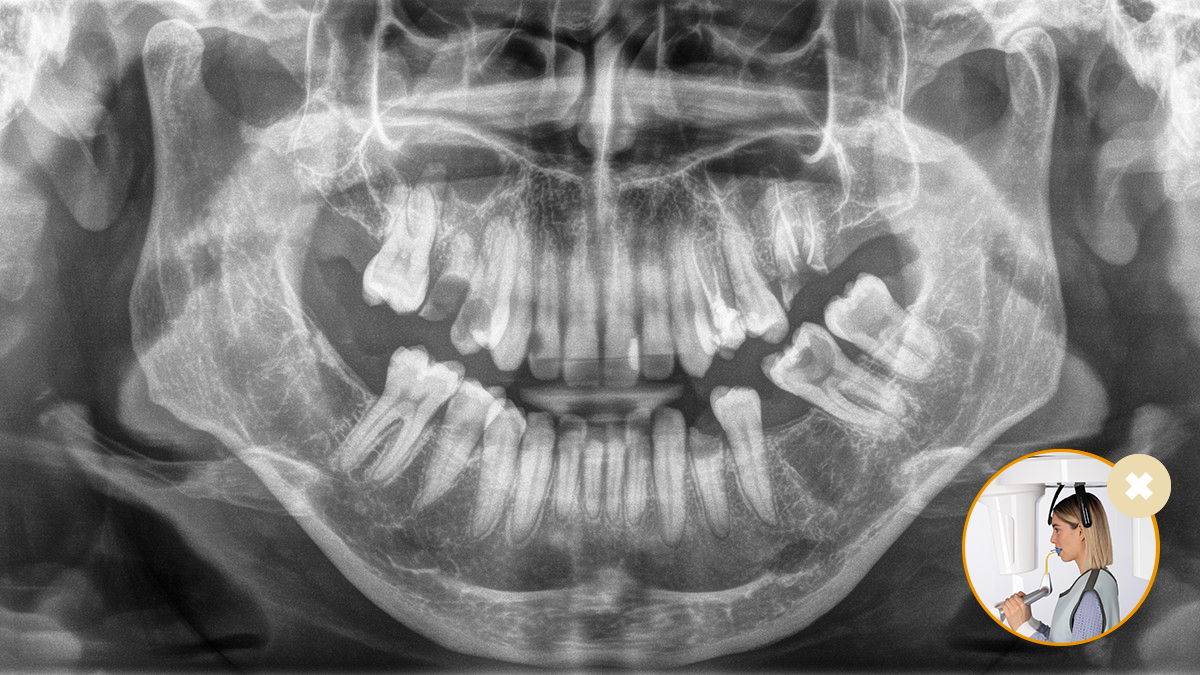

3D Patientenpositionierung mit Universalaufbiss

Bilder der Arbeit mit unserem Patientenpositionierungs- und Bildassistenten-Konzept